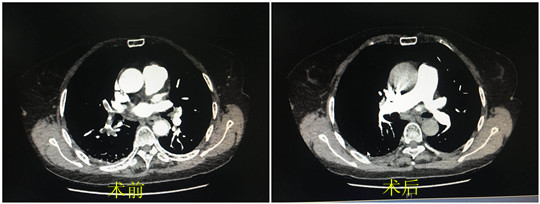

手术非常成功。术后张大娘在CCU医护人员精心治疗下,病情一天天好转。经复查肺动脉CTA,提示栓子较前明显吸收。张大娘很快康复出院,重新回到了正常的生活中。